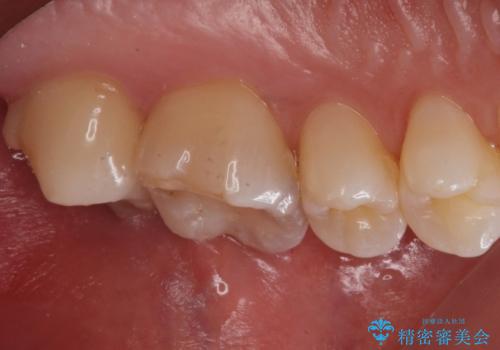

白い詰め物が入り、ザラザラもなくなりました。

一つ手前の古いプラスチックで治療されている歯も現在詰め物にやりかえを検討中です。